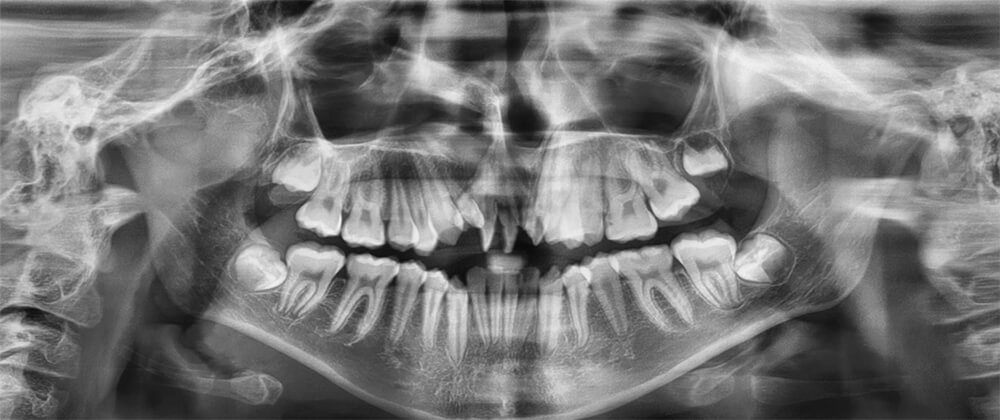

Estudios radiográficos iniciales en la radiografía panorámica se ven 34 dientes presentes; con los terceros molares en formación presencia de dientes supernumerarios en la zona anterosuperior figura 6.

Fig. 6 Rx Panorámica